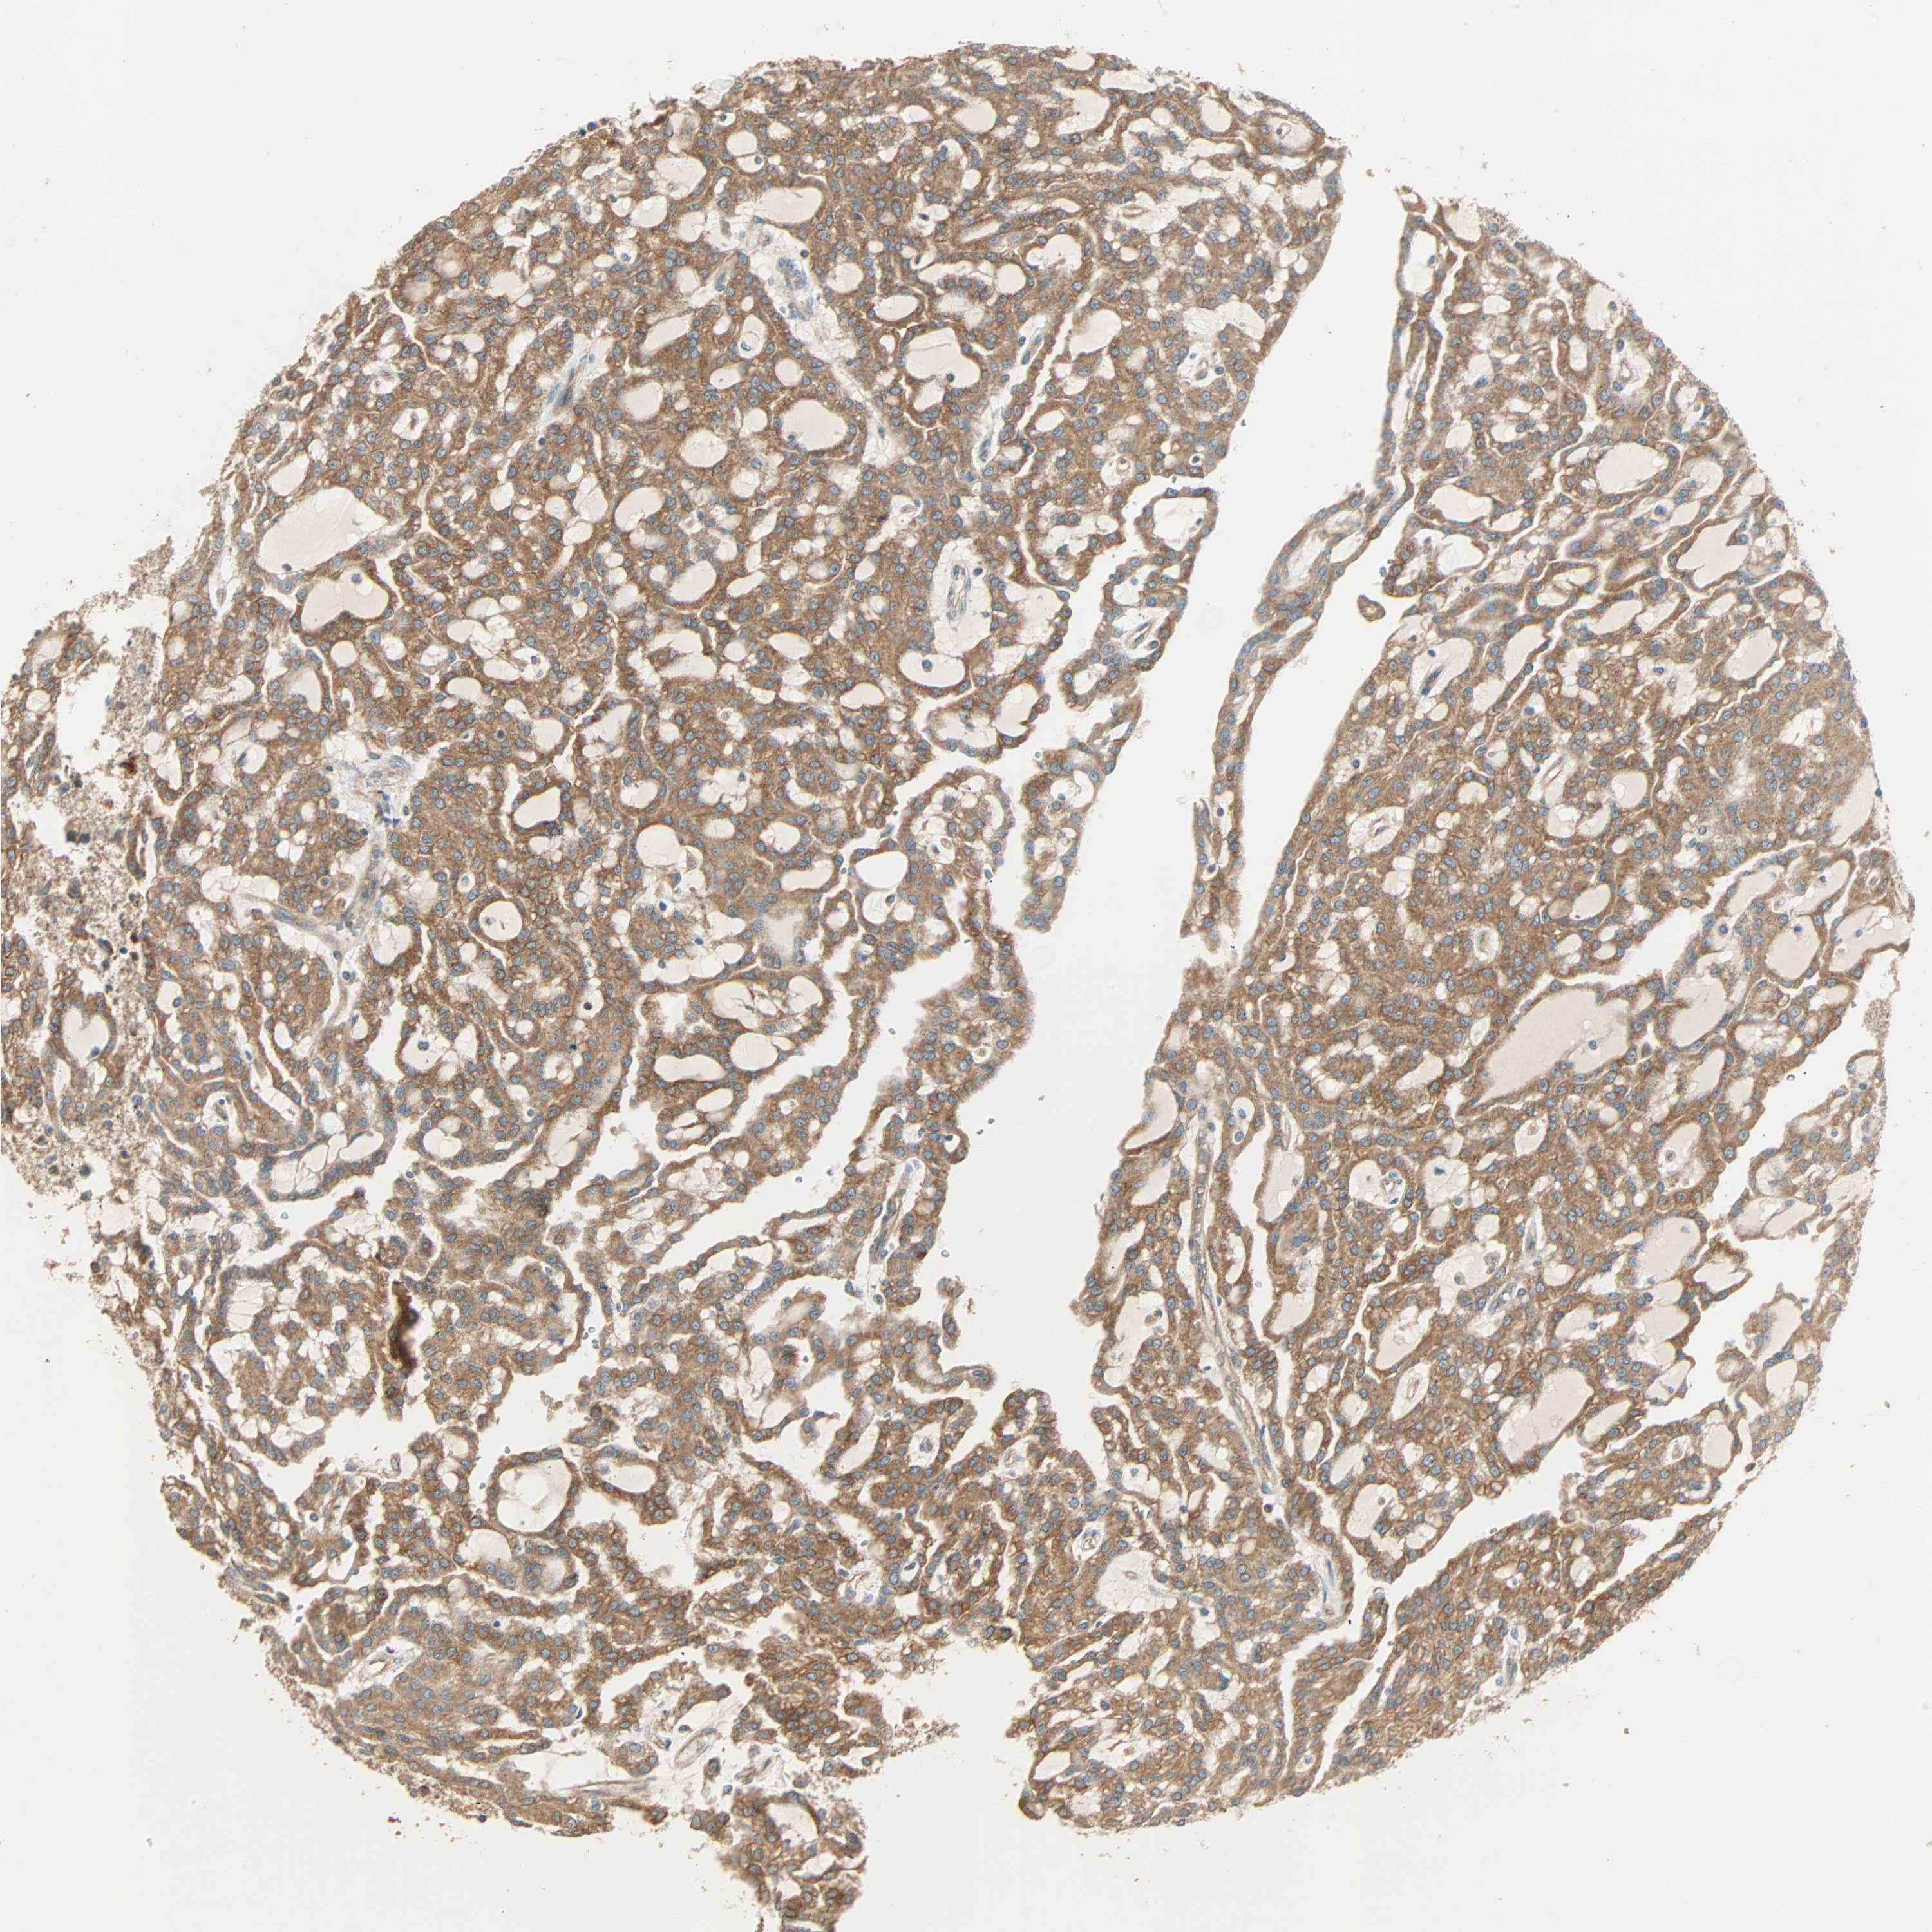

CANCER RENAL CANCER Show tissue menu

KICH TCGA KIRC TCGA KIRC VALIDATION KIRP TCGA PROTEIN RCC CPTAC PROTEIN EXPRESSION